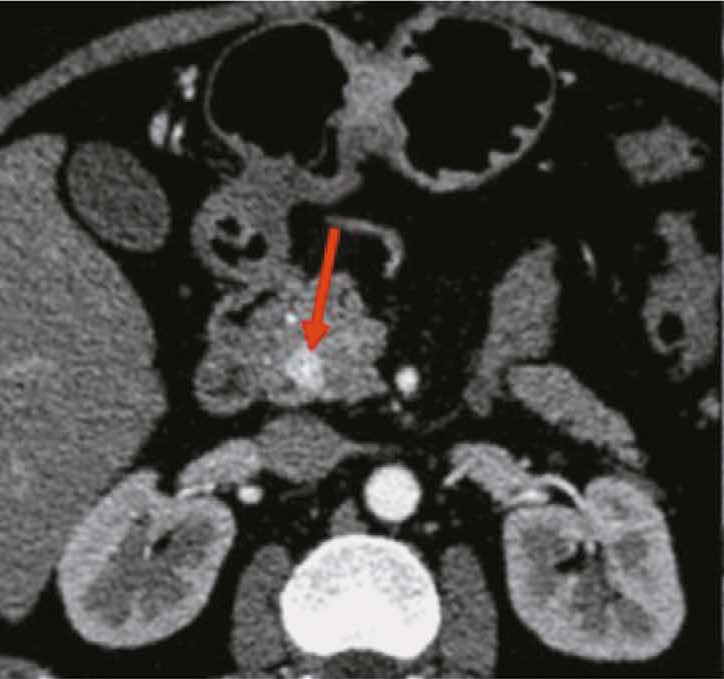

BACKGROUND: Radiomics is currently a promising and prospective tool for diagnosing and treating neuroendocrine neoplasms at various sites. This method is often used for differential diagnosis of gastrointestinal neuroendocrine tumors with other neoplasms at this site.

AIM: The aim of the study was to evaluate the potential of radiomics for differential diagnosis of neuroendocrine tumors of stomach and pancreas.

MATERIALS AND METHODS: The study included data of 12 patients with morphologically proven neoplasms of the stomach (6 with neuroendocrine tumors and 6 with adenocarcinomas) and data of 22 patients with morphologically proven neoplasms of the pancreas (11 with neuroendocrine tumors and 11 with adenocarcinomas). All patients underwent abdominal computed tomography (CT) with intravenous contrast enhancement prior to treatment at the Russian Scientific Center of Roentgenology and Radiology. Radiomics parameters were calculated for the area of gastric and pancreatic tumor manually segmented in the native phase of the CT scan. The results were processed and statistically analyzed using Microsoft Office Excel and R-Studio, a free, open-source software development environment for the R programming language.

RESULTS: CT scan examples demonstrate typical and atypical visual signs of neuroendocrine tumors of stomach and pancreas, contrast enhancement characteristics, location and structure of neoplasms. Fifteen radiomics parameters were identified that were statistically significantly different between gastric neuroendocrine tumor and gastric adenocarcinoma. In pancreas, neuroendocrine tumors differed significantly from adenocarcinomas in 14 radiomics parameters.

CONCLUSIONS: Neuroendocrine tumors of stomach and pancreas are rare neoplasms that are mostly asymptomatic and difficult to visualize due to their small size and contrast enhancement characteristics. Texture analysis may be a promising approach to differentiate gastrointestinal neuroendocrine tumors from other neoplasms at these sites, especially in the view of the difficulty in obtaining a biopsy.